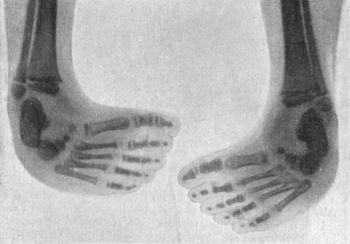

| 142. | Bilateral Congenital Club-foot in an Infant | 274 |

| 143. | Radiogram of Bilateral Congenital Club-foot in an Infant | 275 |